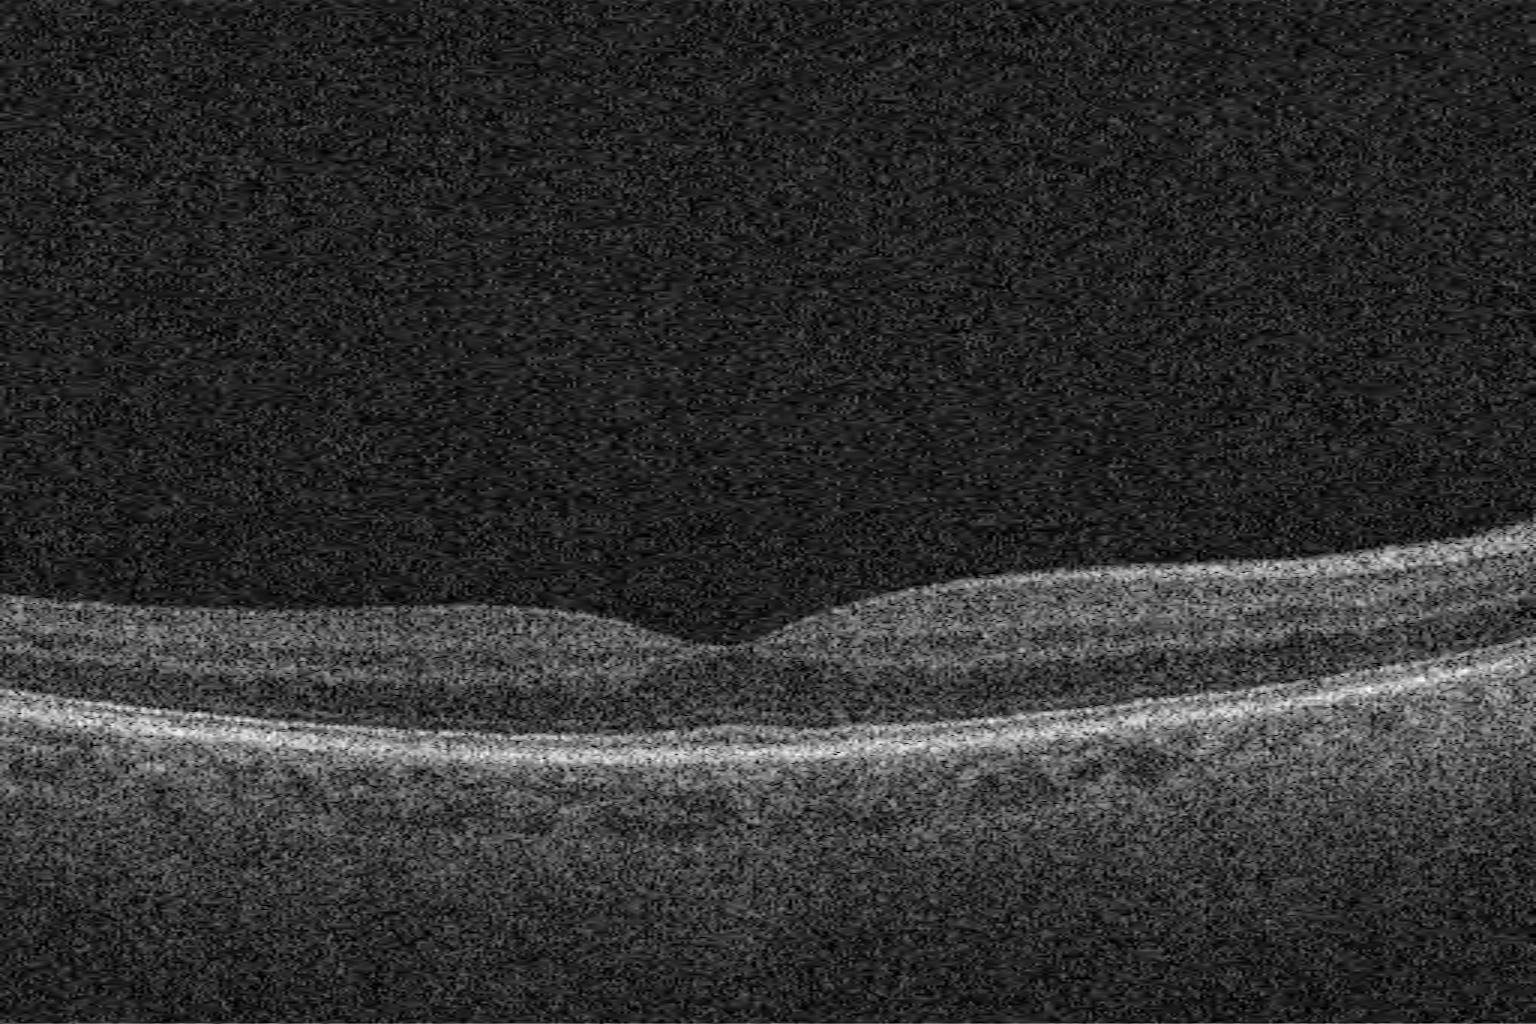

Right eye macular OCT scan from Care1

Examination showed intraocular pressures of 16 mm Hg in both eyes. Optic nerve evaluation revealed slightly asymmetric cupping with thinning of the inferior neuroretinal rim in both eyes. OCT demonstrated minor superior nerve fiber layer thinning, relatively stable since prior visits. Visual field testing revealed superior nasal defects in the right eye and some paracentral defects in the left eye.

Structural and functional assessments remain stable under current therapy.

A patient on Travatan OU shows well-controlled IOP (OD 12–26, OS 14–26 mm Hg). C/D asymmetry is noted (0.40 OD, 0.70 OS), with possible RNFL thinning and mild progression on visual fields in the left eye. The right eye remains stable.

Follow-up every 6–12 months with OCT and visual field testing is recommended. Escalation of therapy may be considered if left-eye changes progress. Reassuring features include stable pressures, advanced age, and a normal right eye.

Asymmetric optic nerve cupping with retinal nerve fiber layer (RNFL) thinning reflects localized loss of retinal ganglion cell axons, often associated with glaucomatous optic neuropathy. Mechanical stress from intraocular pressure and vascular factors can lead to remodeling of the lamina cribrosa and progressive axonal loss. Structural changes include focal or diffuse thinning of the RNFL, enlargement of the optic cup, and notching of the neuroretinal rim. These changes often precede detectable visual field defects and are key early indicators of optic nerve damage.

Early thinning of the retinal nerve fiber layer (RNFL), detectable by OCT, often occurs before visual field loss becomes apparent, making RNFL measurement a powerful early indicator of optic nerve damage.